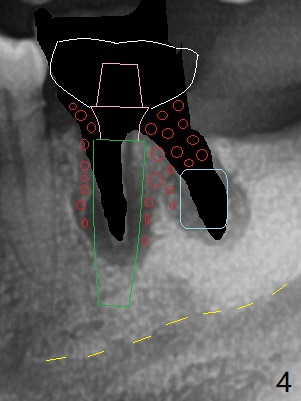

Since the distal crest is low at #19 after extraction (Fig.3), a 4.5x11 mm FC implant (Fig.4 green) will be immediately placed in the mesial socket (lingual), which has more clearance from the Inferior Alveolar Canal (yellow). Sticky bone will be initially up to the implant plateau, followed by insertion of a cemented abutment (pink), placement of the 2nd round of bone graft (red) and fabrication of an immediate provisional (white). To save time, a piece of collagen plug is inserted into the apical portion of the distal socket (blue). The distal crest will be expected to increase ~ 3 mm by the procedure mentioned above. The #32 socket heals with apparent exposure of collagen plug 2 weeks postop (Fig.5). The #27 and 28 sockets heal with fresh granulation tissue 2 weeks postop (Fig.6). The fistula buccal to #28 socket appears to have shrunken 2 weeks postop (Fig.7).